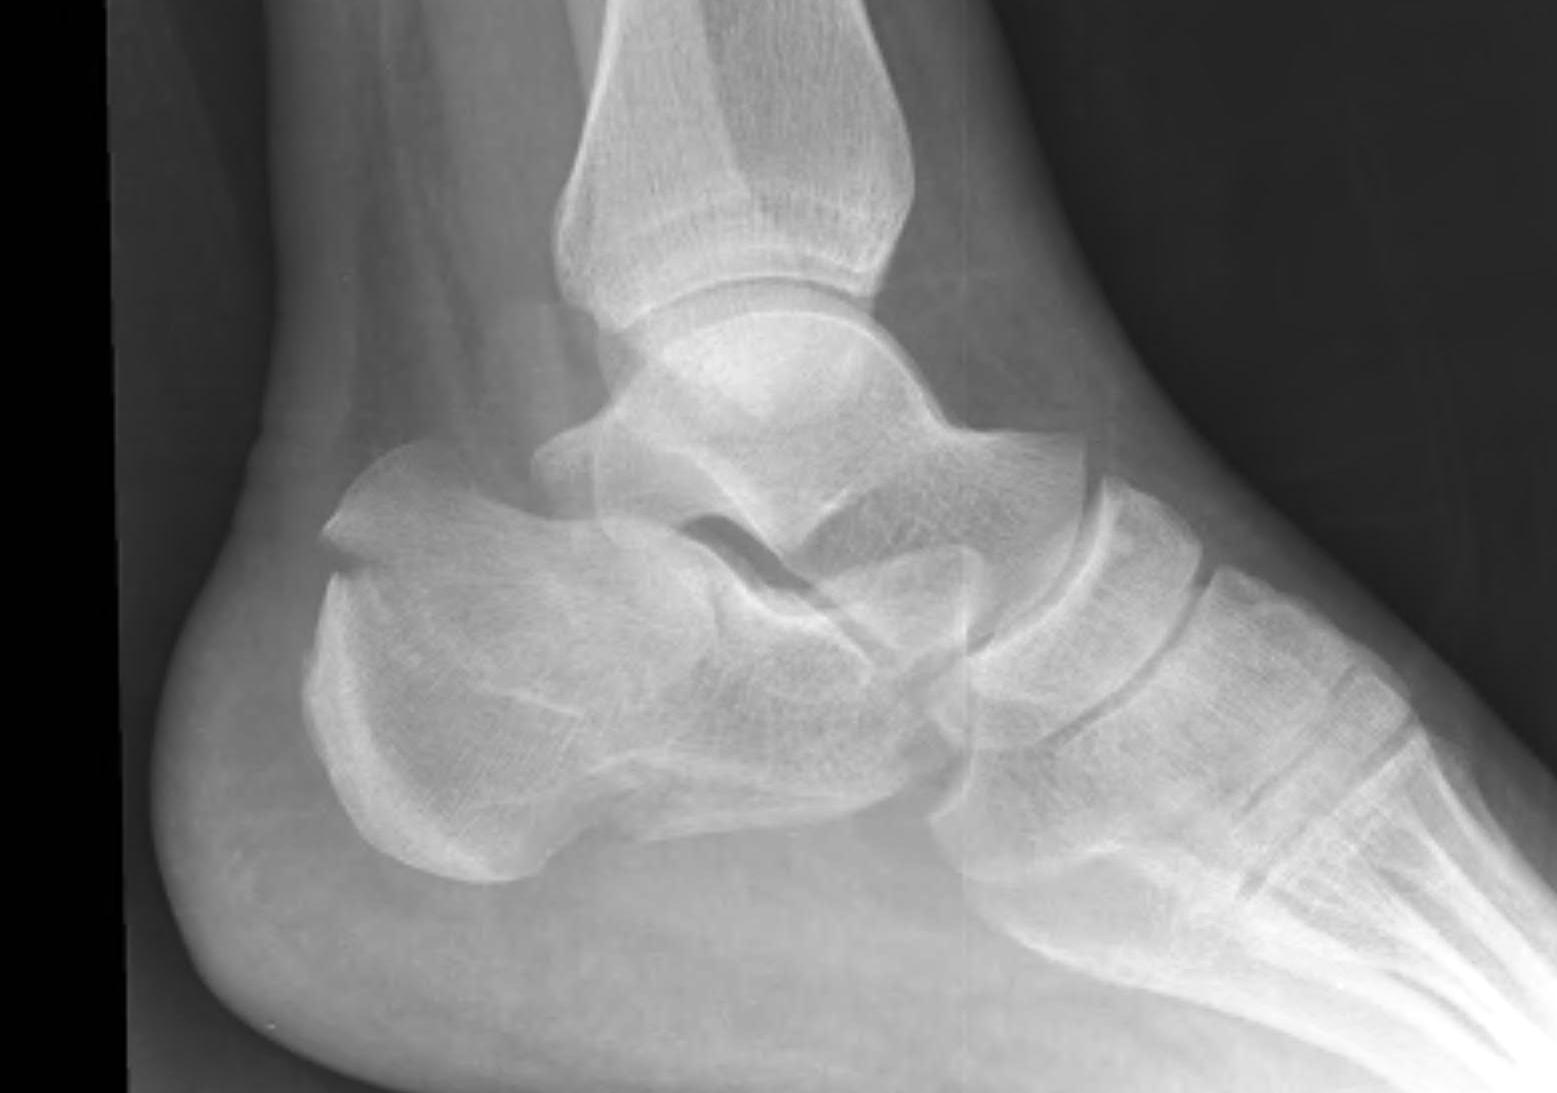

Rockerbottom foot / Persian Slipper Foot

Uncommon

50% bilateral

Doesn't delay walking

- may present in toddler with callus under talus head